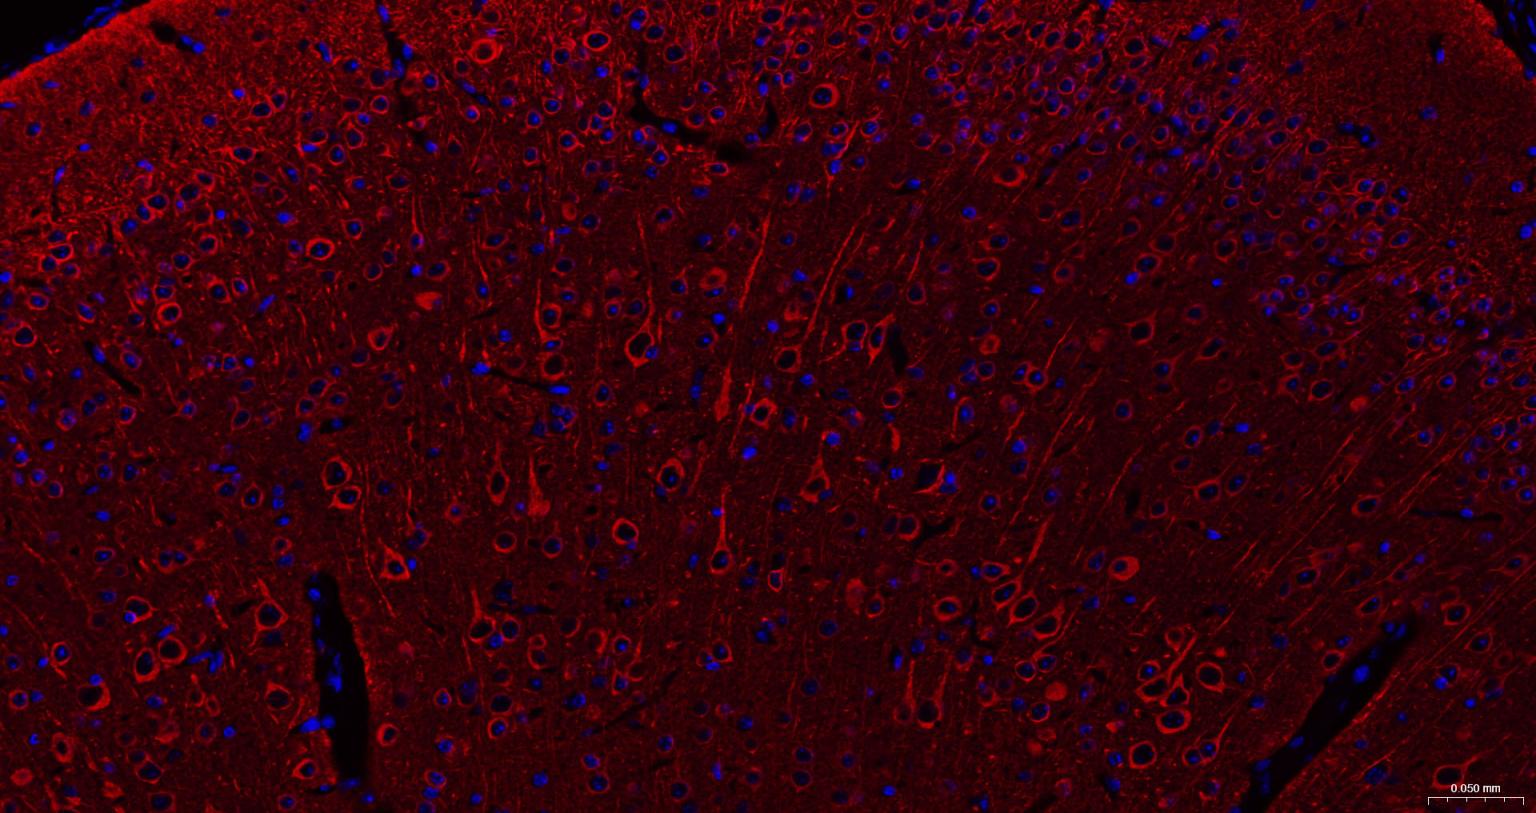

Paraformaldehyde-fixed, paraffin embedded Rat Cerebrum; Antigen retrieval by boiling in sodium citrate buffer (pH6.0) for 15 min; The section was incubated with Tubulin beta-III Monoclonal Antibody, Unconjugated (bsm-52323R) at 1:200 overnight at 4°C. Followed by conjugated Goat Anti-Rabbit IgG antibody (Red, bs-0295G-BF594), DAPI (blue, C02-04002) was used to stain the cell nuclei.